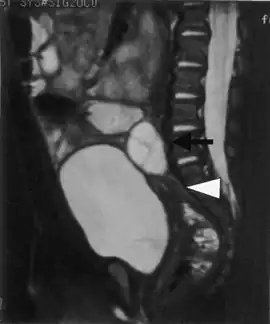

Enlarged cystic ovaries and normal sized uterus